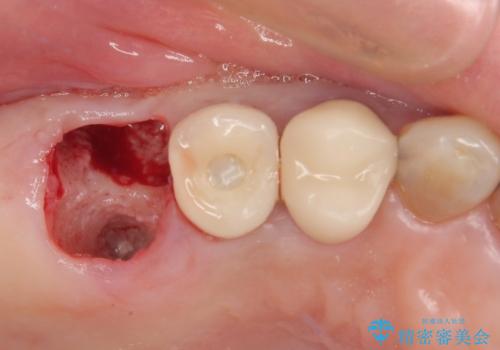

歯肉を開いて確認をしたところ、著しく骨欠損しており、目視でも歯根破折が確認されました。

3つある歯根の内、1つのみに骨欠損がある状態で、インプラント埋入に十分な骨の状態でした。